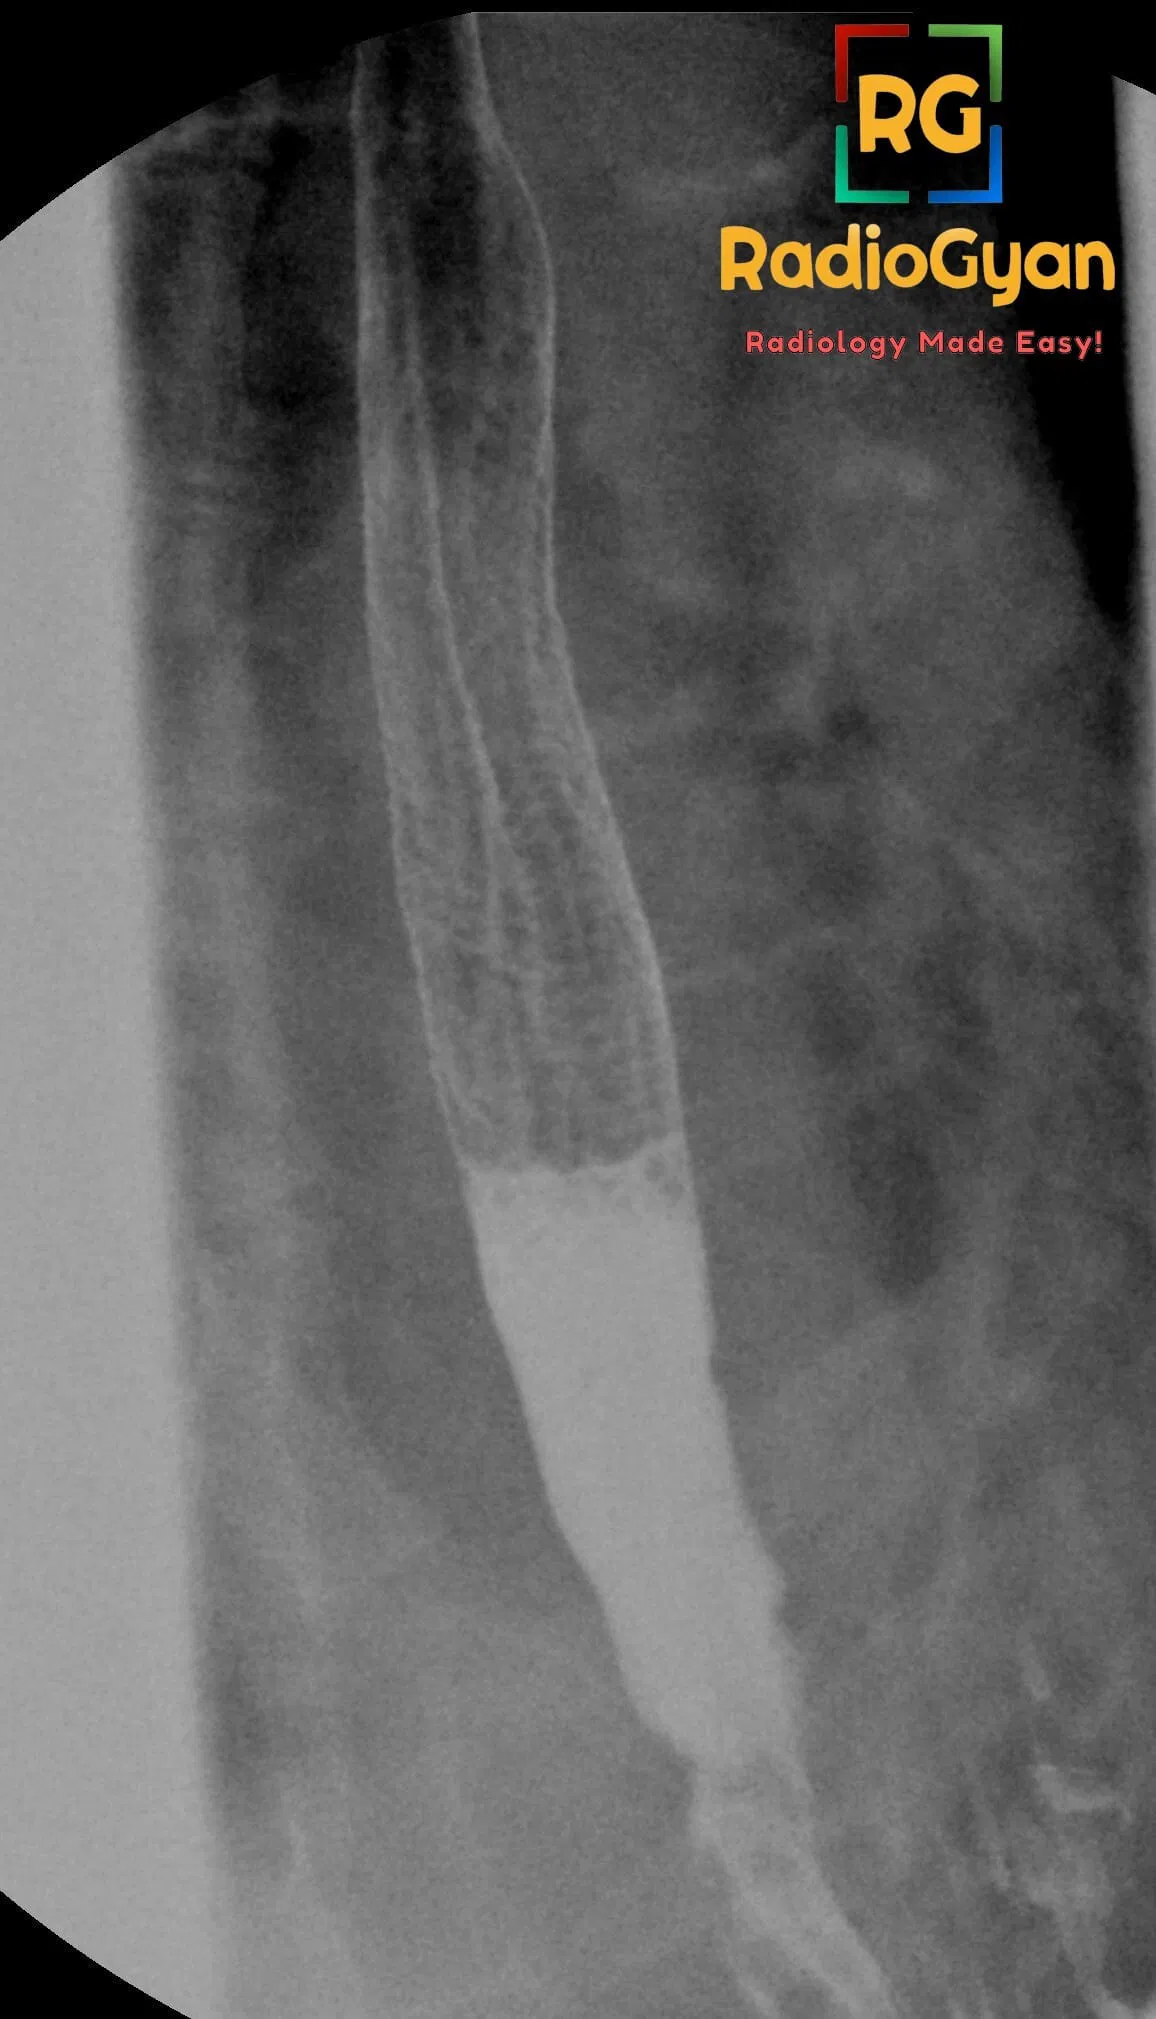

Feline esophagus is caused by the presence of multiple thin, closely spaced transverse mucosal folds seen in the mid to distal thoracic esophagus on double-contrast esophagography. It is most commonly associated with gastroesophageal reflux (GER) and sometimes with hiatal hernia. These folds can appear transiently and represent muscularis mucosa contractions rather than fixed pathology. The clinical condition linked to this sign is gastroesophageal reflux disease (GERD), though it is not directly related to reflux esophagitis or strictures.

It is named “feline esophagus” because the radiographic folds resemble the normal fine transverse folds seen in the esophagus of cats.

The sign arises from concentric horizontal striations due to longitudinal contractions of the muscularis mucosa layer, causing transient mucosal folds. These folds reflect esophageal motility changes often triggered by acid reflux, but they are usually reversible and not indicative of chronic structural damage. The presence of these folds correlates strongly with episodes of reflux, and patients with marked reflux are more likely to demonstrate the feline esophagus sign.